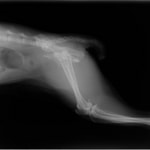

術後レントゲン